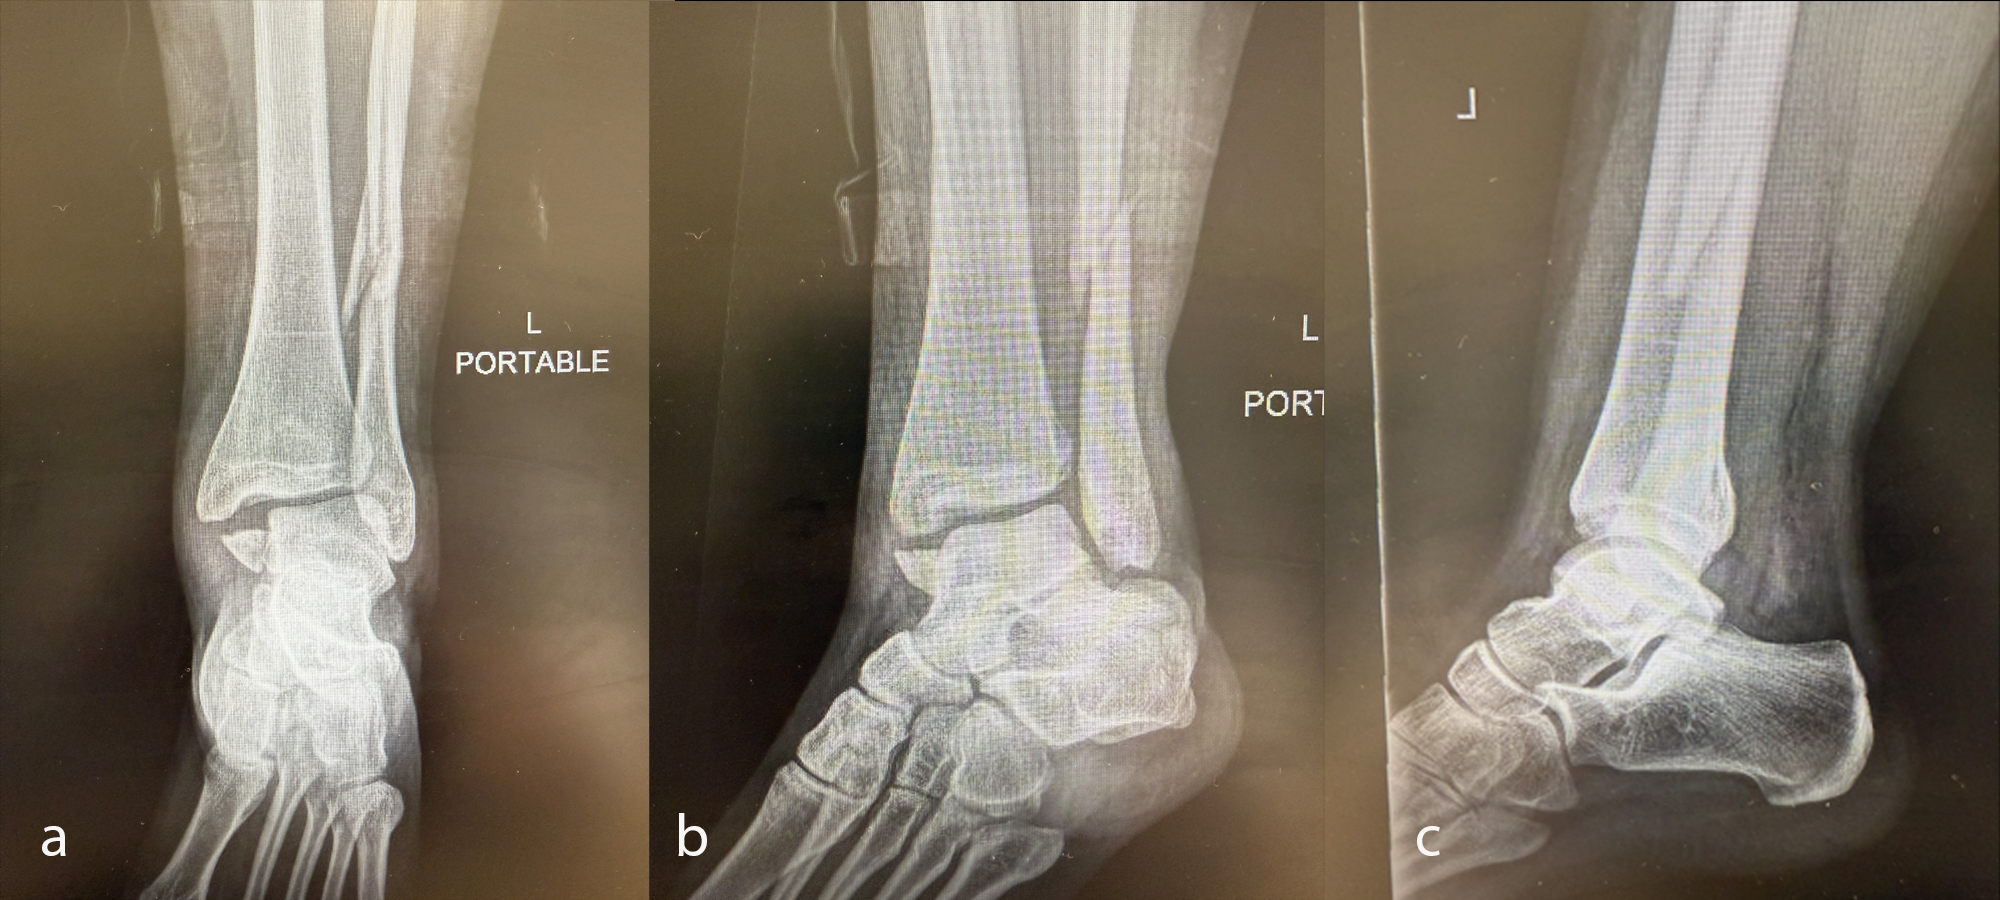

A young adult had an accident, sustaining a trimalleolar ankle fracture with syndesmosis disruption (Fig 33).

Once the soft-tissue swelling had reduced sufficiently, the patient underwent open reduction and internal fixation (ORIF) surgery, with the VOLT™ Mini Fragment hook plate medially and the Small Fragment metaphyseal plate laterally. The syndesmosis was addressed with 4.0 mm screws (Fig 34). The surgery was uneventful and performed on an ambulatory basis.